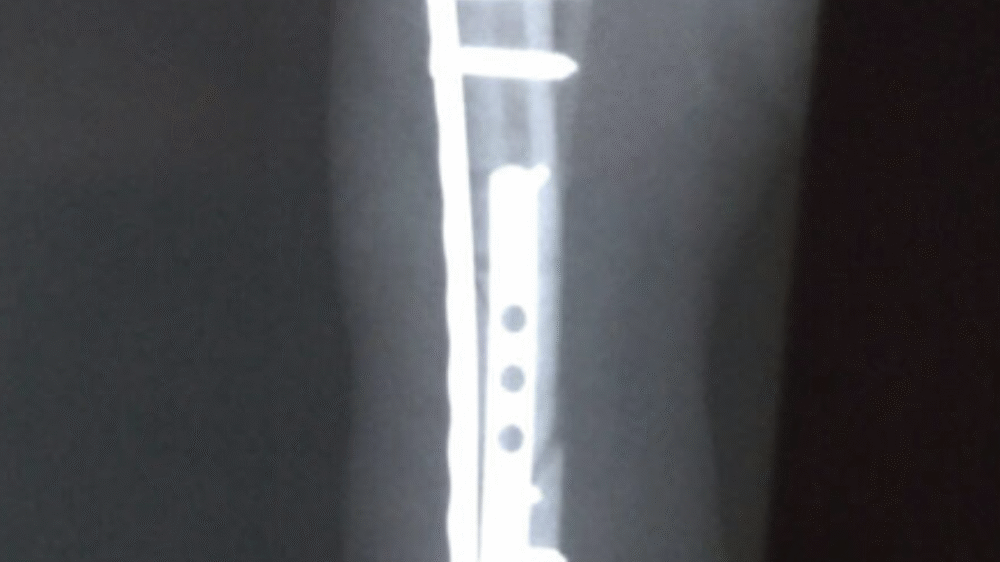

Tibia Fracture Repair